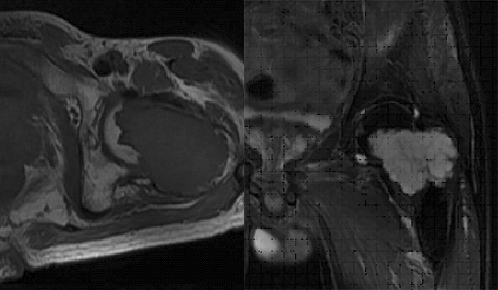

瘤软骨为肿瘤细胞产生的软骨基质,多来源于软骨类肿瘤,或内有化生瘤软骨成分的其他肿瘤如成软骨型骨肉瘤。瘤软骨为软组织密度,未钙化时,主要通过 MRI 检查显示。由于瘤软骨多由富含水分及粘多糖的透明软骨构成,故 T1WI 呈偏低信号,T2WI 或 PDWI 呈明显高信号,被低信号的纤维间隔分开呈分叶状(图 24、图 25a-b),增强扫描多呈不均匀分隔状强化(图 25c),主要是纤维间隔强化,瘤软骨强化不明显之故。

图片

图 24.瘤软骨:内生软骨瘤

图 25.瘤软骨:内生软骨瘤